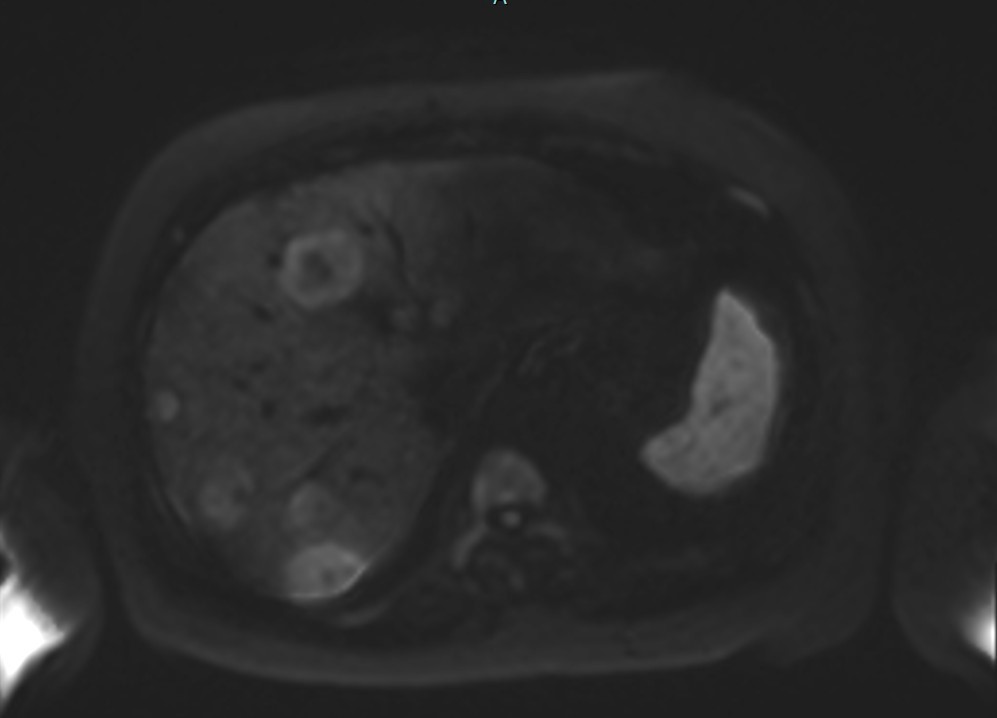

Figure 2d. Axial DWI at b=1500 s/mm² demonstrating maintained lesion visibility with optimal volumetric concordance to PET-CT MTV.